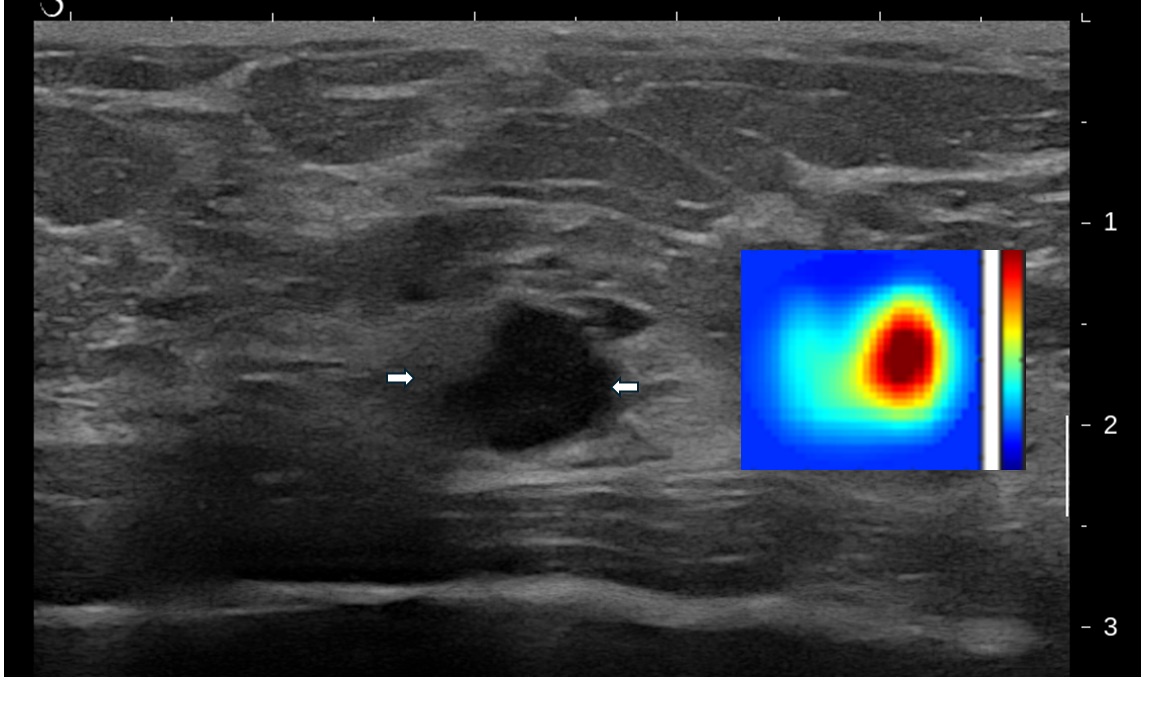

• Breast Cancer: Pioneered the integration of ultrasound and near-infrared (NIR) imaging for clinical diagnosis and for predicting and assessing treatment response in advanced breast cancer, advancing this work into an AI-assisted imaging platform.

• Ovarian Cancer: Led the development of co-registered ultrasound and photoacoustic imaging techniques for accurate diagnosis, including innovations in AI-assisted imaging platforms.